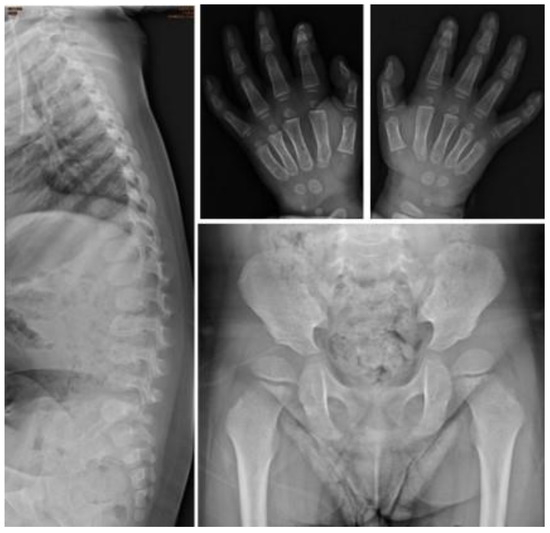

| I-5 | M | c.1400C > T, p.P467L | — | 0.5 | Baseline | 0.2 | 0.27 | 153.16 | 21.4 | 30.01 | 0.11 | Proximal tapering of metacarpal bone with bullet-shaped phalanges. | Normal | Normal | Normal | Normal |

| Follow-up | 3.5 | 7.51 | 18.01 | 0.42 | 3.28 | 2.39 | Suspicious of mild proximal tapering of metacarpal bone with bullet-shaped phalanges. | Multiplex dysostosis of the spine. L-spine vertebral bodies are round. The anterior beaking more at several vertebral bodies of L-spine. | Round iliac wings, inferior tapering of the ilea with not-well developed acetabulum. | Normal | Normal | |||||